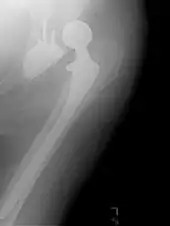

Hip prosthesis for hemiarthroplasty. This example is bipolar, meaning that the head has two separate articulations.

Hip prosthesis for hemiarthroplasty. This example is bipolar, meaning that the head has two separate articulations. X-ray of the hips, with a right-sided hemiarthroplasty

X-ray of the hips, with a right-sided hemiarthroplasty